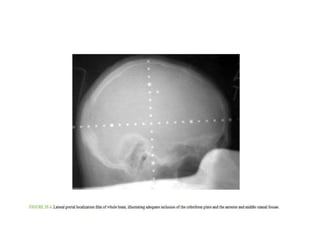

Conventional – Whole Brain Radiotherapy

• Whole-brain irradiation is administered through parallel-opposed

lateral portals. The inferior field border should be inferior to the

cribriform plate, the middle cranial fossa, and the foramen magnum,

all of which should be distinguishable on simulation or portal

localization radiographs.

• The safety margin depends on penumbra width, head fixation, and

anatomic factors but should be at least 1 cm, even under optimal

conditions.

• A special problem arises anteriorly because sparing of the ocular

lenses and lacrimal glands may require blocking with margins <5 mm

at the cribriform plate.

• The anterior border of the field should be approximately 3 cm

posterior to the ipsilateral eyelid for the diverging beam to exclude

the contralateral lens. However, this results in only approximately

40% of the prescribed dose to the posterior eye.

• A better alternative is to angle the beam approximately 3 degrees or

more (100- or 80-cm source-to-axis distance midline, but also field

size dependent) against the frontal plane so that the anterior beam

border traverses posterior to the lenses (approximately 2 cm

posterior to eyelid markers).

• Placing a radiopaque marker on both lateral canthi and aligning the

markers permits individualization in terms of the couch angle.

• This arrangement provides full dose to the posterior eyes. However,

the eyelid-to-lens and eyelid-to-retina topography is individually

more constant than the canthus, and lateral beam eye shielding is

better individualized with the aid of CT or MRI scans.

• When in doubt about tumor coverage or lens sparing for tumors in a

subfrontal or middle cranial fossa location, one should consider CT-

based contouring and planning.